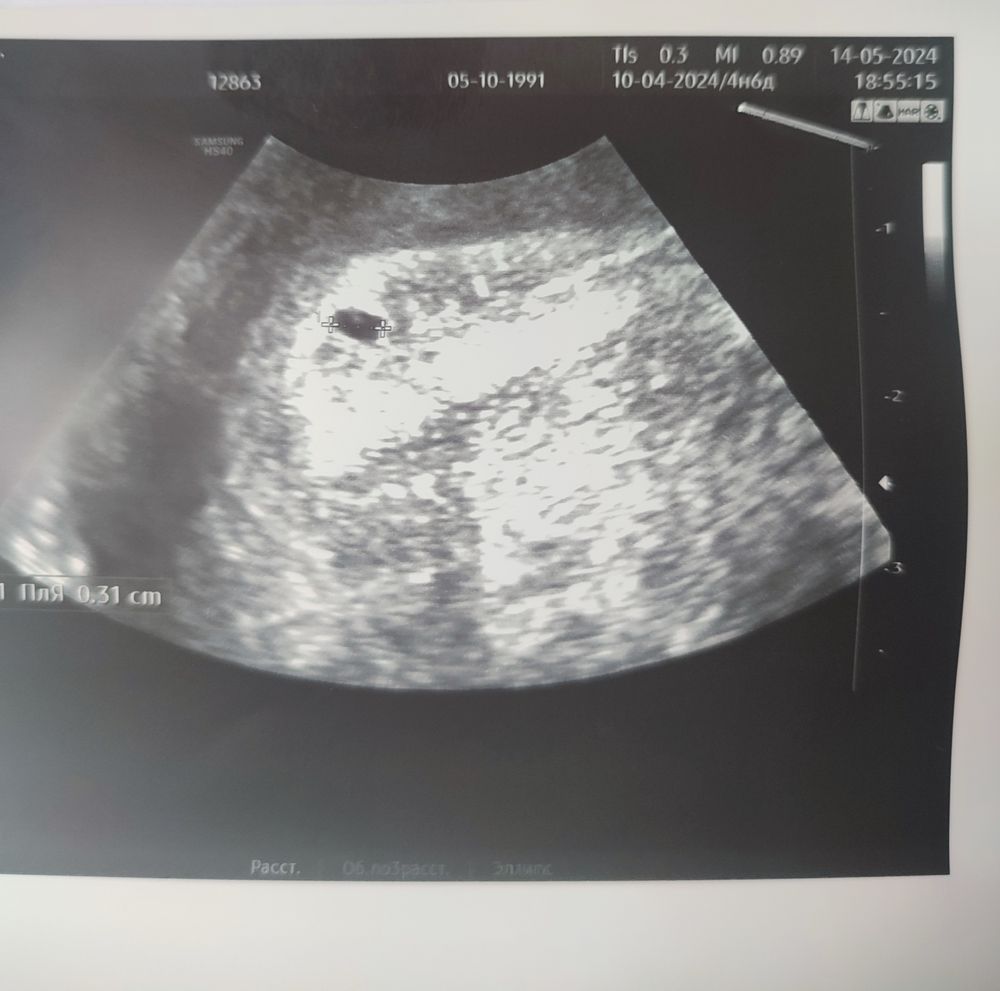

А до этого вы не делали узи? Ну просто вообще не понятно. Размер пя отличный для вашего срока. И как при хгч 440 может быть пя 3 мм🤷‍♀️

ta987nya, не знаю🫣 но я его со всех сторон рассмотрела, это точно плодное яйцо. И даже желточный мешочек очевиден. До этого не делала после переноса.

Екатерина, так ясно же, что пя это. Вы знаете, у меня в последнюю б первое фото сына было именно такое. ПЯ было 4 мм, срок 5 недель. У вас по срокам тоже все совпадает. Но почему такое хгч.....? И вообще не понятно, как при таком хгч может быть пя таких размеров? При хгч 440 вообще ничего не должно быть на узи видно.

Так,а 16дпп это какой срок получается ?4 недели где то? Ну вообще для 16 дпп размер пя соответствует, а для эмбриона ещё может быть рано,так что все может быть)

Счастье Любит Тишину, да я, честно говоря, и ПЯ увидеть не рассчитывала при таком хгч, а тут и ПЯ, и мешочек..но ХГЧ все портит( У меня 4.6 акушерских.

Екатерина, узи отличное, я бы сказала)

Ирина, согласна, узи на хгч гораздо выше